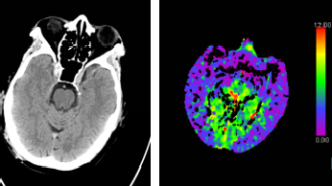

腦部CT檢查即電子計(jì)算機(jī)斷層掃描(Computed Tomography),是一種無(wú)創(chuàng)性檢查方法,通過(guò)X線和計(jì)算機(jī)技術(shù)相結(jié)合,獲取腦部結(jié)構(gòu)的橫斷面圖像,這種檢查方法可以清晰地顯示顱內(nèi)結(jié)構(gòu),對(duì)于診斷腦出血、腦梗塞、腦腫瘤等疾病具有重要意義。

2、局限性:雖然腦部CT檢查具有較高的診斷價(jià)值,但也存在一定的局限性,對(duì)于某些疾病,如早期腦梗塞、輕微腦震蕩等,CT檢查可能無(wú)法準(zhǔn)確診斷,腦部CT檢查主要關(guān)注結(jié)構(gòu)異常,對(duì)于某些功能性問(wèn)題,如認(rèn)知障礙、情緒問(wèn)題等,無(wú)法直接判斷。

腦部CT檢查主要用于診斷腦部結(jié)構(gòu)異常,如果檢查結(jié)果顯示沒(méi)有異常,說(shuō)明在結(jié)構(gòu)上沒(méi)有發(fā)現(xiàn)明顯的病變,這并不意味著大腦一定沒(méi)有問(wèn)題,因?yàn)椋?/p>

1、功能性問(wèn)題:雖然腦部CT可以顯示結(jié)構(gòu)異常,但對(duì)于功能性問(wèn)題,如認(rèn)知障礙、情緒問(wèn)題等,無(wú)法直接判斷,這些問(wèn)題可能與腦部功能失調(diào)有關(guān),但CT檢查無(wú)法發(fā)現(xiàn)。

2、其他檢查方法:除了腦部CT檢查外,還有其他檢查方法,如腦電圖(EEG)、磁共振成像(MRI)等,可以輔助診斷腦部疾病,這些檢查方法可以檢測(cè)腦部功能異常和某些細(xì)微結(jié)構(gòu)變化。

3、疾病發(fā)展階段:某些疾病在早期可能無(wú)明顯結(jié)構(gòu)異常,但隨著病情發(fā)展,可能會(huì)出現(xiàn)明顯的結(jié)構(gòu)變化,即使腦CT檢查結(jié)果正常,也不能完全排除患病的可能性。